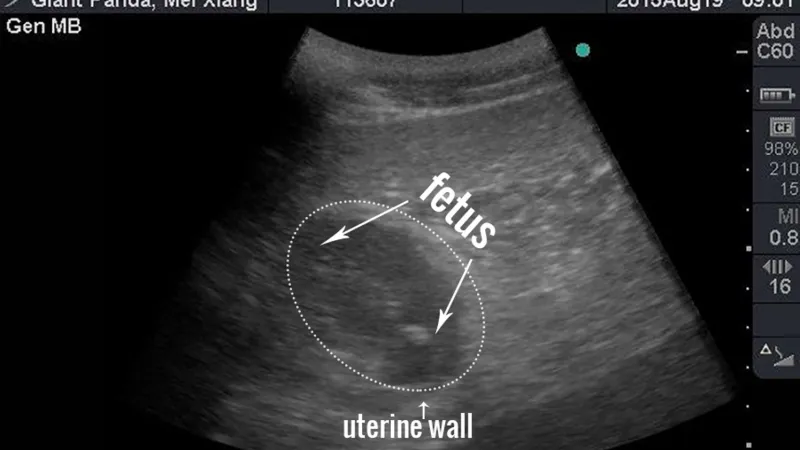

Ve washingtonské zoo se v sobotu narodily dvě pandy, pohlaví zatím chovatelé neurčili. Druhé z později narozených mláďat je v inkubátoru. Matkou je slavná panda Mei Xiang, která už dříve přivedla na svět dva živé přírůstky. Samice byla tentokrát uměle oplodněna směsí spermií dvou samců. Podle agentury Reuters vrhla sedmnáctiletá panda mláďata v rozpětí několika hodin.

Mei Xiang byla tentokrát uměle oplodněna směsí spermií dvou samců pandy velké, čínského samečka Chuej-chuej a Tian Tiana z washingtonské zoo. Personál zoo ponechává pandě a jejím potomkům soukromí, zasáhl by pouze, pokud by nastaly náhlé komplikace.